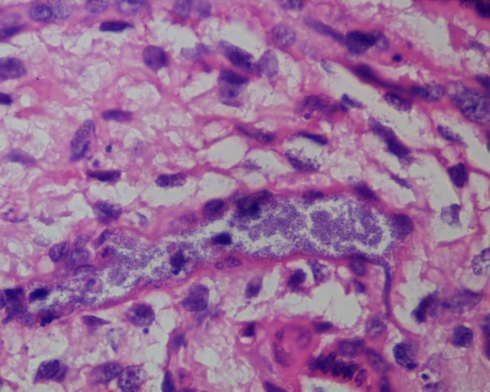

Since posting I found a few more unscanned images that I wanted to share.

The central villus shows that the lymphocytes just beneath the syncytium are T-lymphocytes, and are associated with a breach in a the lower portion of the syncytium. (CD-3, 20x)